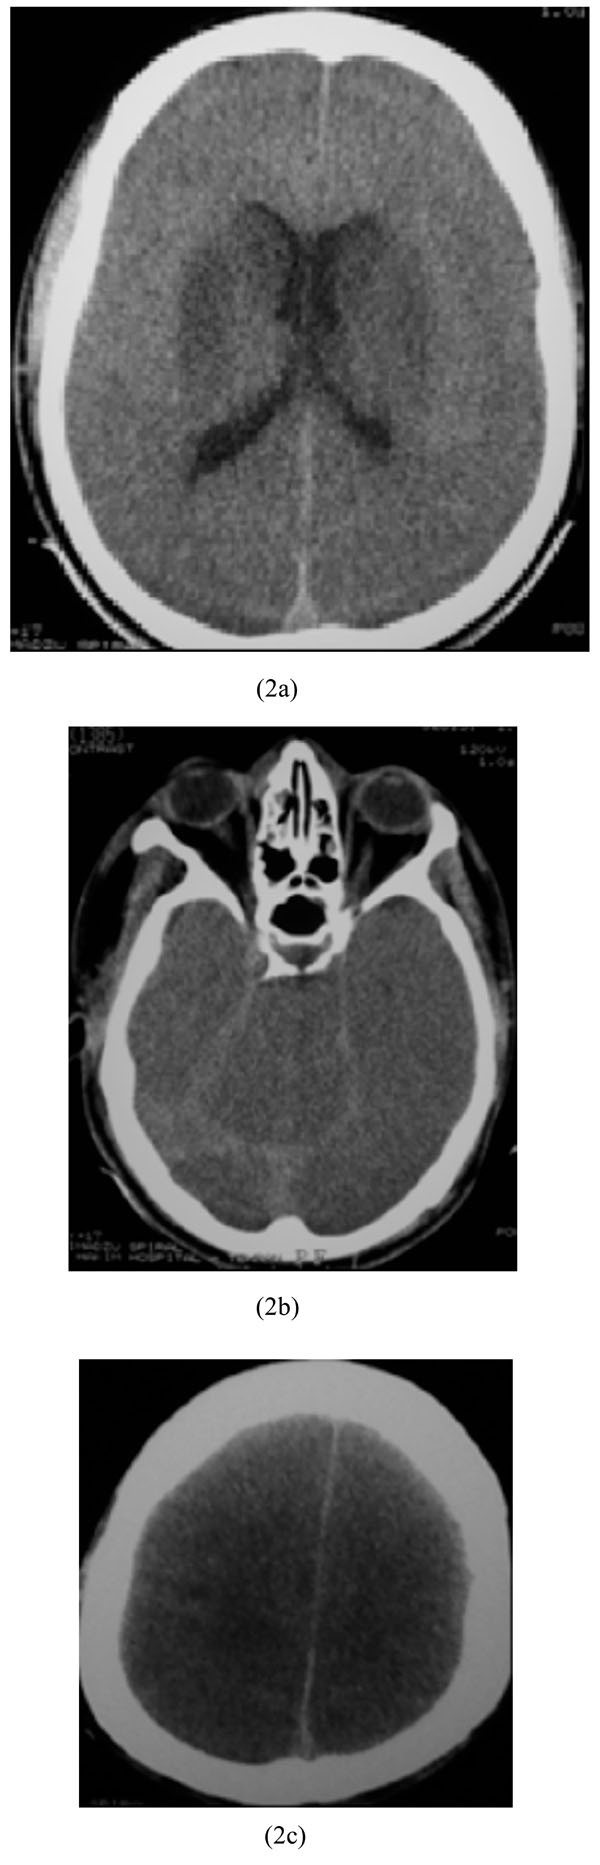

A 19-year-old man with no significant past medical history was presented in a comatose state nearly two hours after ingestion of 1200 mg of propranolol in a suicidal attempt. He experienced cardiac arrest in another hospital, for which successful cardiopulmonary resuscitation (CPR) was performed, before referral to our center. At admission, vital signs showed a systolic BP of 50 mmHg, and a RR of 30/minute, with a filiform pulse. Pupils were symmetric without any reaction to light. He underwent brain CT scan which revealed bilateral basal ganglia hypodensities and cytotoxic edema with pseudo-subarachnoid hemorrhage sign (Figs. 2a-2c). After eight days of receiving supportive treatments, the patient died due to cardiac arrest.

Bilateral basal ganglia hypodensities and cytotoxic edema with pseudo-subarachnoid hemorrhage sign in propranolol intoxication.